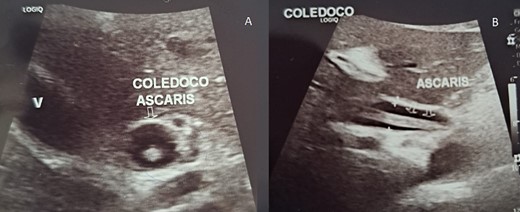

With these findings, it was necessary to perform an ultrasound. It revealed a distended gallbladder with sludge and a dilated common bile duct. A straight, non-shadowing echoic cord-like structure without a central hypoechoic tube was noticed within it (Figs 1a and 2b).

(A) Echography shows the bile duct dilated with the Ascaris inside it; (B) echography is a straight, non-shadowing echoic cord-like structure in the bile duct.